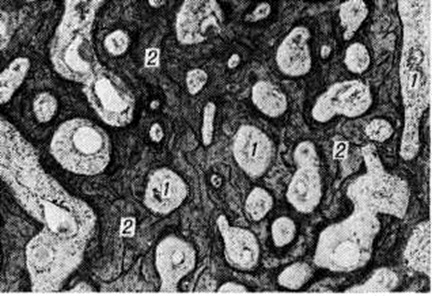

Паростальная саркомаПаростальная саркома (греческий para около + osteon кость; саркома; синонимы: оссифицирующая паростальная остеома, параоссальная саркома, паростальная остеобластическая саркома, паростальная остеогенная саркома, юкстакортикальная остеогенная саркома) — злокачественная остеогенная опухоль, развивающаяся из камбиального слоя надкостницы. Выделена из группы остеогенных сарком в 1951 год Гешиктером и Коуплендом (Ch. F. Geschickter, М. М. Copeland). Паростальная саркома встречается относительно редко, преимущественно в возрасте 30— 50 лет, несколько чаще у женщин, составляет до 3—6% всех первичных костных сарком. Опухоль чаще поражает диафизы длинных трубчатых костей, особенно часто — дистальный диафиз бедренной кости. Макроскопически образована плотными костными массами и отдельными мягкими узлами, связанными с периостом и не поражающими корковое вещество кости. По гистологический строению напоминает компактную остеому (смотри полный свод знаний), но в Паростальная саркома пространства между костными перекладинами обычно заполнены опухолевой остеогенной тканью с анаплазией различной степени. Иногда эта ткань приобретает сходство с тканью фибромы или фибросаркомы; часто в ней встречаются островки, напоминающие хондросаркому. Костное вещество опухоли имеет относительно зрелую структуру, но отличается беспорядочным расположением костных перекладин (рисунок 1). В клинические, картине многие исследователи выделяют первоначальную фазу, в течение которой опухоль медленно растёт без выраженных проявлений. Боль, как правило, отсутствует или бывает умеренной. Когда опухоль достигает значительных размеров, появляются симптомы, связанные со сдавлением нервных стволов и кровеносных сосудов, появляются боли, которые усиливаются и становятся постоянными. Рентгенологические картина в начальных стадиях развития опухоли характеризуется наличием в мягких тканях вблизи кости солитарного, грибовидной формы, чётко отграниченного плотного опухолевого образования (рисунок 2). У его полюсов между опухолью и корковым веществом подлежащей кости видна линия просветления. В дальнейшем кость окутывают наподобие муфты опухолевые массы с отчётливыми очертаниями, состоящие как бы из сливающихся шаров и полушарий различных размеров. Структура опухоли в центральной её части плотнее, однороднее, чем в периферической. Периостальной реакции не наблюдается. Паростальная саркома метастазирует гематогенно в лёгкие, где метастазы могут быть обнаружены при рентгенологическое исследовании.